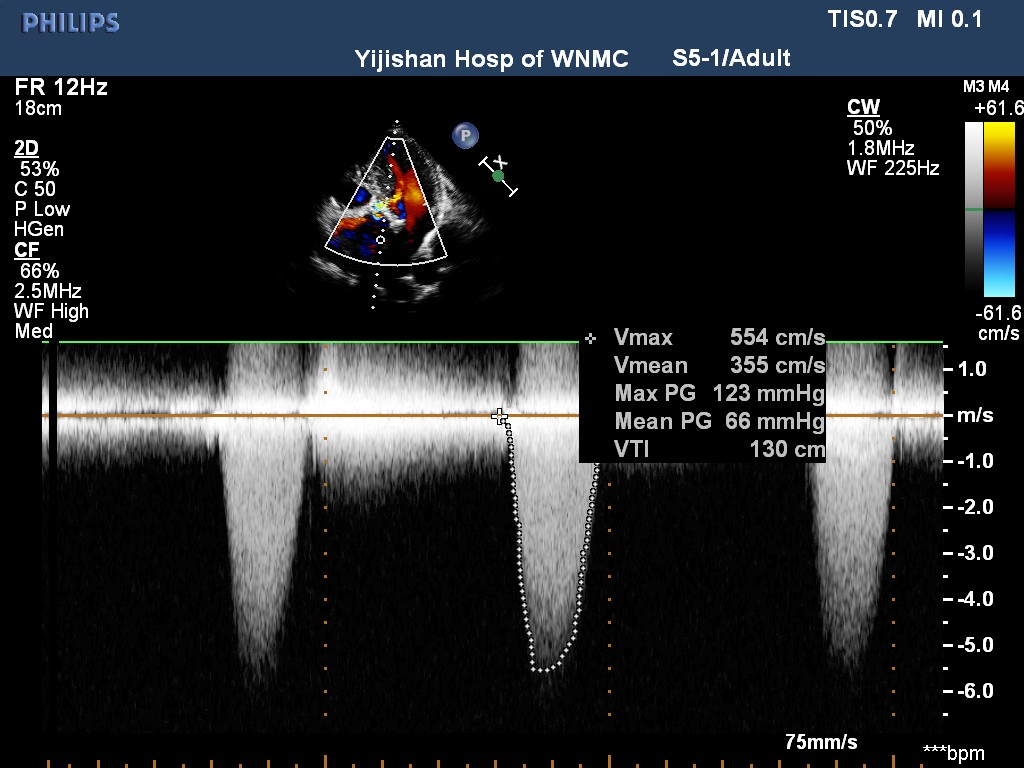

心脏彩超示:升主动脉硬化并增宽,左房增大;主动脉瓣钙化伴重度狭窄,轻度反流。

最高跨瓣压差:123mmHg;